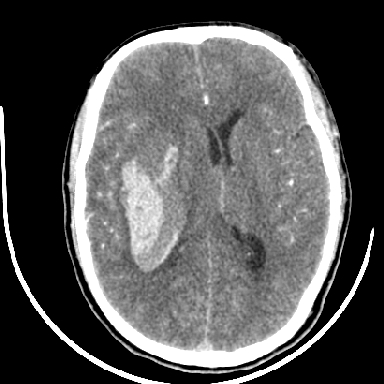

标题: CT6056:脑出血(血管畸形?) [打印本页]

标题: CT6056:脑出血(血管畸形?)

m 40突发头痛左侧偏瘫3小时

考虑高血压性脑出血,依据:

1是高血压性脑出血的好发部位,形态呈肾形,是高血压性脑出血的常见形状

2增强时占位效应加重了,考虑出血还没有停止

3病灶周围水肿不是太厉害,一般肿瘤出血水肿多非常明显

4病灶周围的‘软组织’影没有明显的强化

5至于脑血管畸形引起的出血,暂时没有看到明显的畸形血管影,也不太支持

支持右侧基底节脑出血

右侧基底节区脑出血.

支持右侧基底节区(主要为外囊区)原发性脑出血。

另附部分资料:“血液溢出血管外形成血肿,其内含有大量血红蛋白、血浆白蛋白,球蛋白,因这些蛋白对x线的吸收系数高于脑质,故ct呈现高密度阴影,ct值达40~90h,最初高密度灶呈非均匀一致性,中心密度更高,新鲜出血灶边缘不清。基底节区血肿多为“肾”型,内侧凹陷,外侧膨隆,因外侧裂阻力较小,故向外凸,其它部位血肿多呈尖圆形或不规则形”

术中抽出40ml陈旧血液,血肿底部似见一条索血管影